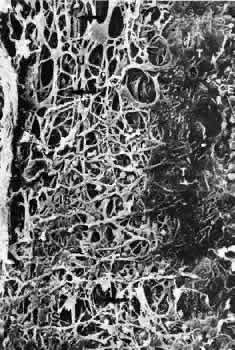

Scanning electron micrographs of serial layers through the entire meshwork and tangential sections (parallel to the inner wall of Schlemm's canal) reveal that the form of the trabecular lamellae and of the intertrabecular spaces changes markedly from the inner to the outer portions of the meshwork. The innermost iridial meshwork consists mostly of long, radial, interconnecting strands forming an irregularly arranged network with rather large openings (Figs. 3 and 4). In the uveal portion, flat sheets are evident that are still relatively irregularly arranged but frequently interconnect with each other. The holes within the uveal meshwork are somewhat smaller than in the iridial meshwork but still show diameters varying between 10 and 30 μm.

Fig. 4. Scanning electron micrograph of the human trabecular meshwork. Internal aspect from the chamber angle side (× 1,640). CE, corneal endothelium; IS, iridial strands (remnants of pectinate ligament); U, uveal meshwork; arrows, corneoscleral meshwork. (Modified from Lütjen-Drecoll E, Rohen JW: Morphology of aqueous outflow pathways in normal and glaucomatous eyes. In Ritch B, Shields MB, Krupin T (eds): The Glaucomas, vol 1, pp 41–74. St. Louis, CV Mosby, 1989)